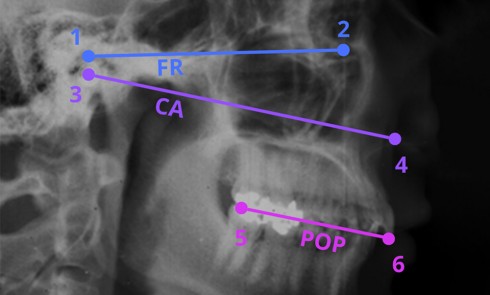

La mise en œuvre d’un traitement prothétique implique la collecte de données biologiques (fonctionnelles et esthétiques), afin de créer une...